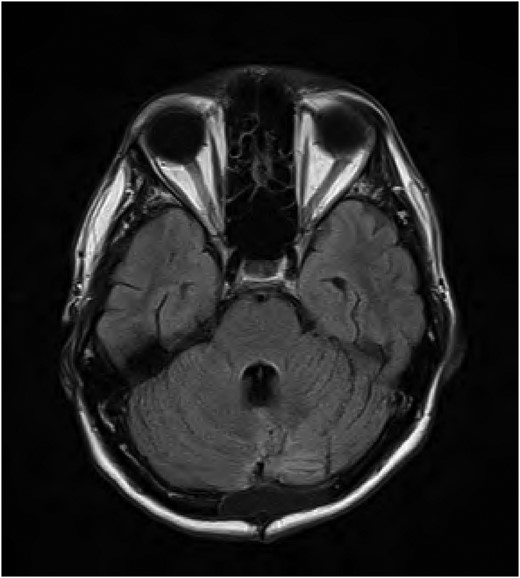

Magnetic resonance imaging (MRI) of the brain performed Day 2 post procedure showed fluid-attenuated inversion recovery sequence (FLAIR) abnormality within the floor of the fourth ventricle, on the dorsal pons, involving the facial colliculus (Fig. 1).

FLAIR MRI brain showing high signal abnormality in the floor of the fourth ventricle.